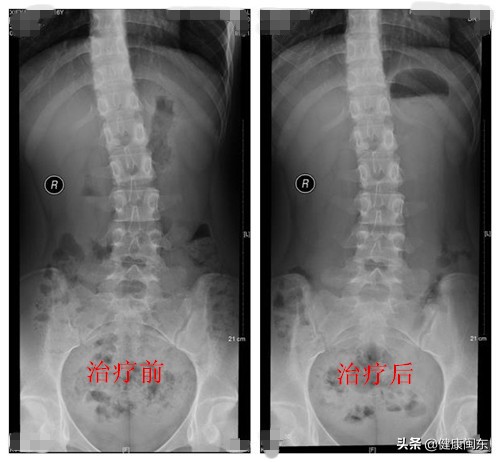

毕研贞表示,保持良好的姿势、肌肉拉伸及训练、肌筋膜手法治疗、骨盆调整、整脊等是轻度脊柱侧弯康复治疗方法。青少年患者更应该做到早发现早干预,可以通过站立位比较双侧肩膀是否等高,高低肩时应该警惕;身体前屈测试,站立位向前弯腰,观察背部是否对称,若一侧高起提示脊柱侧弯可能;步态观察,观察步行时是否有身体倾斜或轻微跛行等进行家庭筛查,比对后发现异常,应及时到医院检查。再则,功能性脊柱侧弯在卧位时可能减轻或消失,拍X光片时应采取站立位。(刘明升)